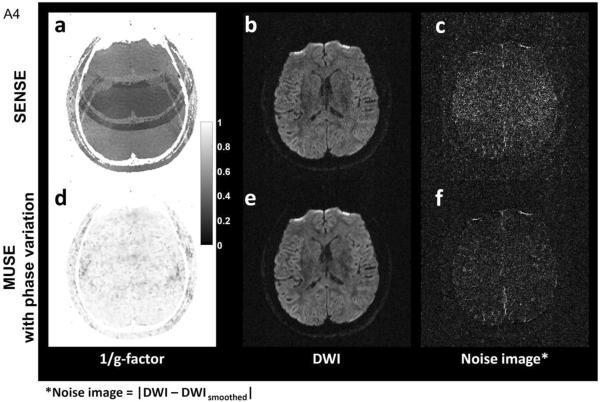

Motion immune diffusion imaging using augmented MUSE for high-resolution multi-shot EPI

“Motion immune diffusion imaging using augmented MUSE for high-resolution multi-shot EPI” authored by Shayan Guhaniyogi et al. has been published in Magnetic Resonance in Medicine.